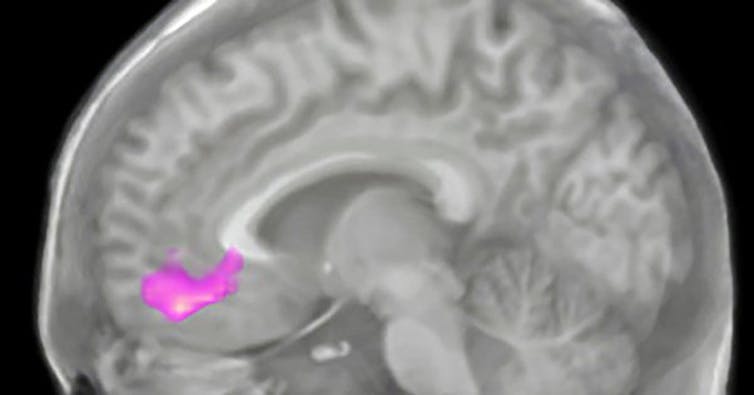

It turns out that the neural connection between gratitude and giving is very deep, both literally and figuratively. A region deep in the frontal lobe of the brain, called the ventromedial prefrontal cortex, is key to supporting both. Anatomically, this region is wired up to be a hub for processing the value of risk and reward; it’s richly connected to even deeper brain regions that provide a kick of pleasurable neurochemicals in the right circumstances. It holds abstract representations of the inner and outer world that help with complex reasoning, one’s representation of oneself and even social processing.

Beyond identifying the place in the brain that was especially active during these tasks, we also saw differences in just how active this region was in various individuals.

We calculated what we termed a “pure altruism response” by comparing how active the reward regions of the brain were during “charity-gain” versus “self-gain” situations. The participants I’d identified as more grateful and more altruistic via the questionnaire had a higher “pure altruism” scores – that is, a stronger response in these reward regions of the brain when they saw the charity gaining money. It felt good for them to see the food bank do well.

Importantly, the participants in our study also exhibited a change in how their brains responded to giving. In the MRI scanner, the group that practiced gratitude by journaling increased their “pure altruism” measure in the reward regions of the brain. Their responses to charity-gain increased more than those to self-gain.

I imagine the ventromedial prefrontal cortex is like the office where you exchange dollars to pounds or vice versa. For the people with more grateful and altruistic tendencies, it seems the ventromedial prefrontal cortex assigns more value to charitable donations than to receiving money for themselves.

Practicing gratitude shifted the value of giving in the ventromedial prefrontal cortex. It changed the exchange rate in the brain. Giving to charity became more valuable than receiving money yourself. After the brain calculates the exchange rate, you get paid in the neural currency of reward, the delivery of neurotransmitters that signal pleasure and goal attainment.